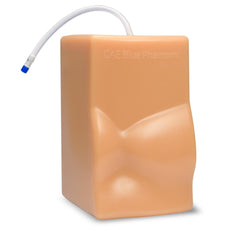

These bone-fracture training blocks help learners develop and practice the psychomotor skills necessary to gain ultrasound proficiency, including using ultrasound system controls, positioning and moving the transducer, recognizing bone fractures and manipulating fractured bones to identify normal versus abnormal imaging characteristics. Choose from two options: Greenstick Fracture, or Crepitus Fracture.

RESPECTIVE ANATOMY:Crepitus Bone Fracture

Greenstick Bone Fracture

Size: 7" long x 5" wide x 2.5" high (17 cm long x 13 cm wide x 6 cm high)

Weight: 3 lbs. (1.3 kg)